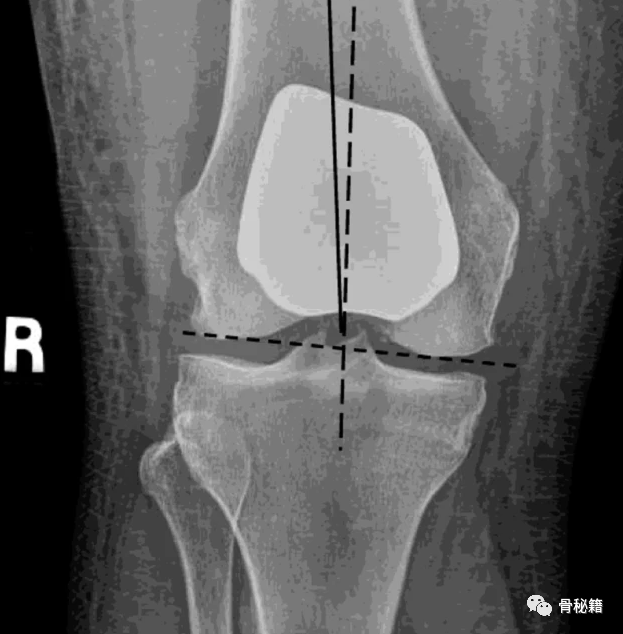

PFA 股骨组件与股骨远端关节线(虚线)对齐,而不与股骨轴线(实线)对齐